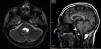

Caso clínicoPresentamos el caso de un varón de 29 años de edad que fue intervenido de un osteoma de mandíbula a los 19 años de edad, y a quien posteriormente se le diagnosticó síndrome de Gardner. Ingresó en nuestro hospital con una paresia facial derecha de un día de evolución acompañada de diplopía. La exploración neurológica confirmó la existencia de una paresia leve del VI y VII pares craneales derechos. La resonancia magnética cerebral mostró una lesión sólido-quística, redondeada, de contorno bien definido, de unos 2cm de diámetro que ocupaba el cuarto ventrículo. El paciente fue intervenido mediante una craneotomía fosa posterior, abordaje telovelar y extirpación completa del tumor implantado a nivel del techo del cuarto ventrículo. El estudio anatomopatológico definitivo informó de un craneofaringioma adamantinomatoso.

Case reportThe case is presented on 29 year-old male who underwent surgery for a jaw osteoma when he was 19 years old and was subsequently diagnosed with Gardner's syndrome. He was admitted in our Hospital with right facial paresis and diplopia of one day onset. The examination showed mild right VII and VI cranial nerves paresis. Magnetic resonance imaging of the brain demonstrated a rounded solid and cystic lesion with well-defined contours of about 2cm in diameter filling the fourth ventricle. The patient underwent a posterior fossa craniotomy using a telovelar approach with complete removal of the tumour implanted at roof level of the fourth ventricle. The final histology of the tumour was reported as adamantinomatous craniopharyngioma.